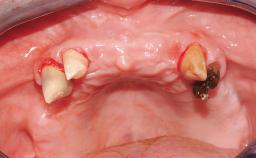

Immediate Loading of Six Implants in the Mandible and Six Implants in the Maxilla and Final Restoration with Full-Arch CAD/CAM Metal Framework FDPs Involving Digital Planning and Guided Surgery

Immediate loading of dental implants is increasingly popular with clinicians and patients. The idea of delivering a restoration directly after implant insertion,combined with a less invasive procedure (flapless protocol), has made treatment protocols involving dental implants more accessible to dentists and patients. However,immediate-loading concepts require sophisticated and exact planning. To facilitate this, conventional panoramic tomographs and periapical radiographs are often taken with the patient wearing a radiographic template simulating the preoperative prosthetic design. However, these radiographs do not provide all the necessary information. In addition, some protocols call for conventional surgical templates fabricated on the diagnostic cast. These will inform the bone drilling points and drill angles, but do not reference the underlying anatomical structures or provide exact 3-D guidance.

Case Type Edentulous Maxilla